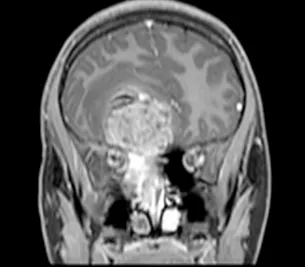

脑部和鼻旁窦计算机断层扫描(CT)和磁共振成像(MRI)扫描显示右侧存在5.5×4.4×5.6厘米肿块,起源于鼻腔、筛窦和蝶窦区域。肿块已侵蚀筛板进入前颅窝。该肿块在CT扫描上未出现钙化(图1),与脑组织等密度,伴有不均匀对比增强。肿块在T1和T2加权MR图像上(图2、3、4)与脑组织等信号,钆增强后显示不均匀强化。注意到周围存在血管源性脑水肿和占位效应。脊柱MRI未见转移证据。

图2:冠状位T1加权钆增强MRI扫描,证实起源于鼻腔并延伸至前颅窝的大肿瘤团块。对额叶下部的占位效应和轻微中线移位明显可见。